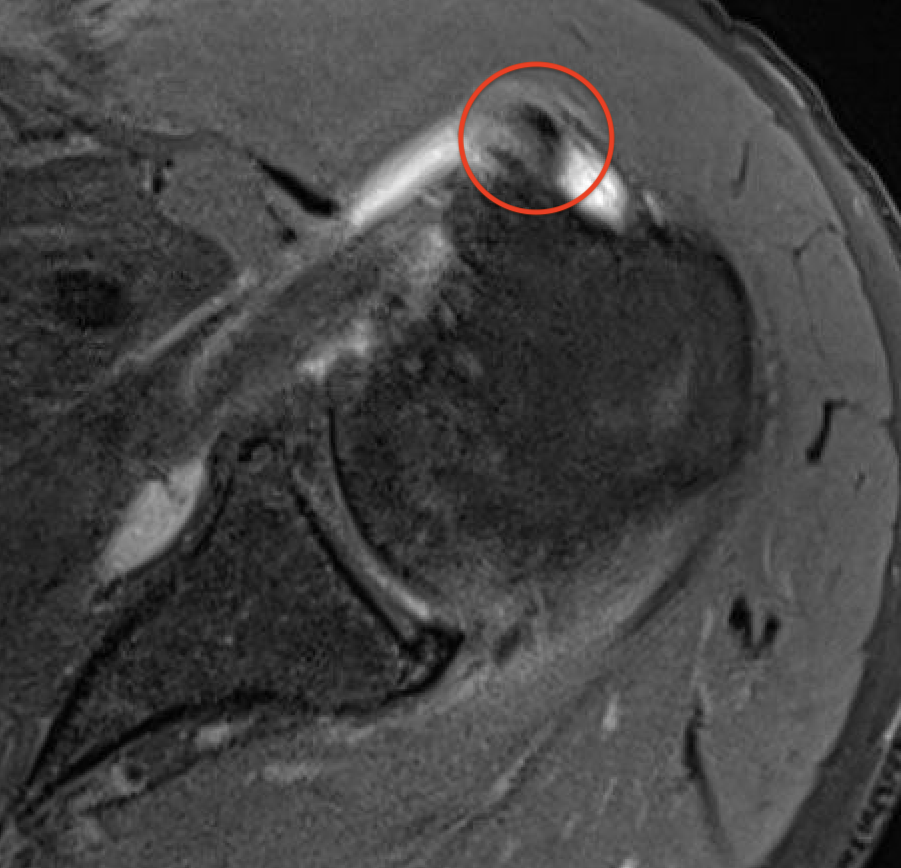

Medial subluxation with subscapularis tear

Kang et al Skeletal Radiol 2017

- accuracy of MRA for 100 patients with LHB subluxation at arthroscopy

- 83% sensitive